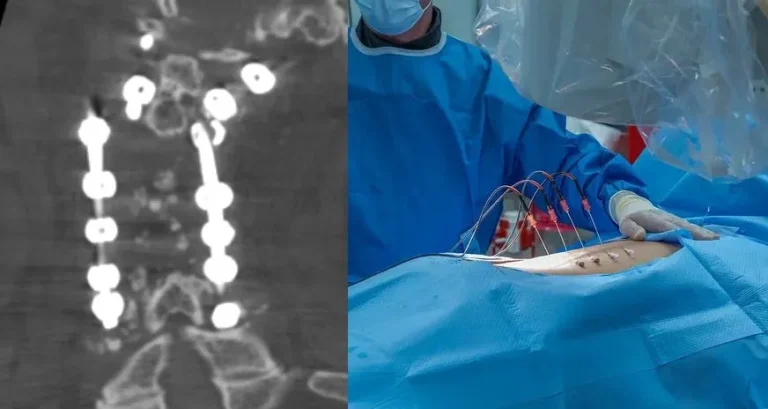

Spinal surgery image with X-ray of metal implants and a surgeon operating on a patient.

CT scan showing spinal instrumentation with screws and rods in place.

ALIF: Highest Complication Rate

90%+ Need Additional Surgery